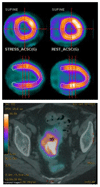

Radioisotopes of elements from all parts of the periodic table find both clinical and research applications in radionuclide molecular imaging and therapy (nuclear medicine). This article provides an overview of these applications in relation to both the radiological properties of the radionuclides and the chemical properties of the elements, indicating past successes, current applications and future opportunities and challenges for inorganic chemistry.